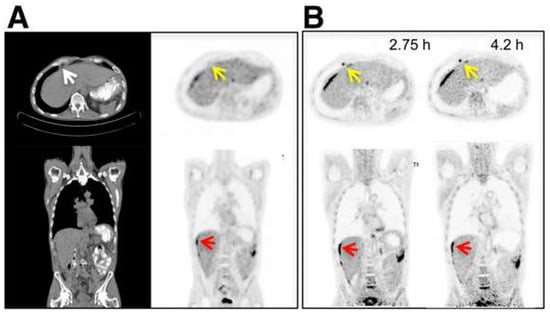

4. Longitudinal and Delayed Imaging

- Houshmand, S.; Salavati, A.; Segtnan, E.A.; Grupe, P.; Hoilund-Carlsen, P.F.; Alavi, A. Dual-time-point Imaging and Delayed-time-point Fluorodeoxyglucose-PET/Computed Tomography Imaging in Various Clinical Settings. PET Clin. 2016, 11, 65–84. [Google Scholar] [CrossRef]

- Soffers, F.; Helsen, N.; Van den Wyngaert, T.; Carp, L.; Hoekstra, O.S.; Goethals, L.; Martens, M.; Deben, K.; Spaepen, K.; De Bree, R.; et al. Dual time point imaging in locally advanced head and neck cancer to assess residual nodal disease after chemoradiotherapy. EJNMMI Res. 2022, 12, 34. [Google Scholar] [CrossRef]